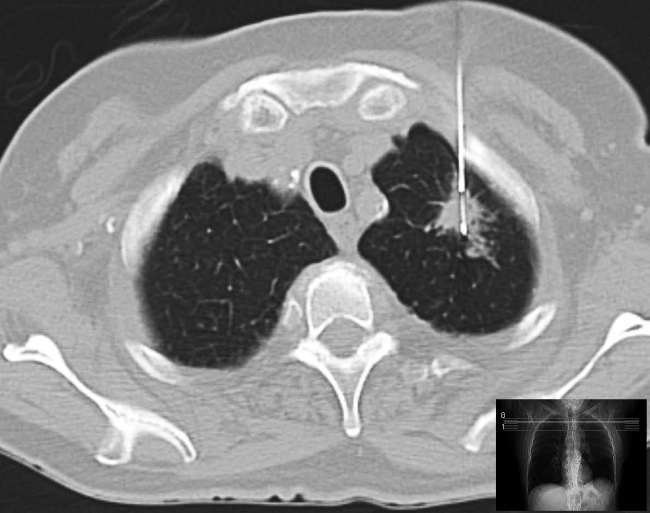

У каждого больного раком есть такой парафиновый блок – образец опухоли, по которому был установлен первоначальный диагноз. Следующее изображение – снимок биопсии легкого. В данном случае для забора образца опухоли используется игла.

Иллюстрация к книге — Завтра начинается сегодня. Как воспользоваться достижениями anti-age медицины [i_021.jpg]

Компьютерная томография процесса биопсии легкого, проведенного по подозрению на рак легких. Справа – игла, входящая в легочную массу. Небольшое изображение внизу справа показывает, где именно сделан большой снимок (в том месте, где линия пересекает пациента).